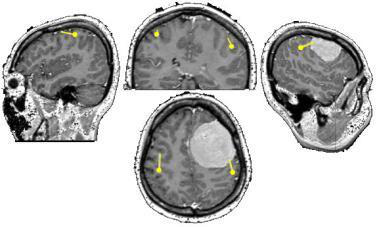

镰旁脑膜瘤通常由脑膜中动脉、胼胝体边缘动脉、胼胝体周围动脉的多个终末动脉分支和前镰动脉的分支提供丰富的供血,这可能使任何手术切除变得复杂。到达后进行的成像显示右侧...

脑膜瘤手术可能在技术上具有挑战性,精心规划的术前计划以及对神经血管解剖结构的仔细注意对于较大限度地提高成功率和降低发病率至关重要。注意静脉解剖会避免对皮质静脉的意...